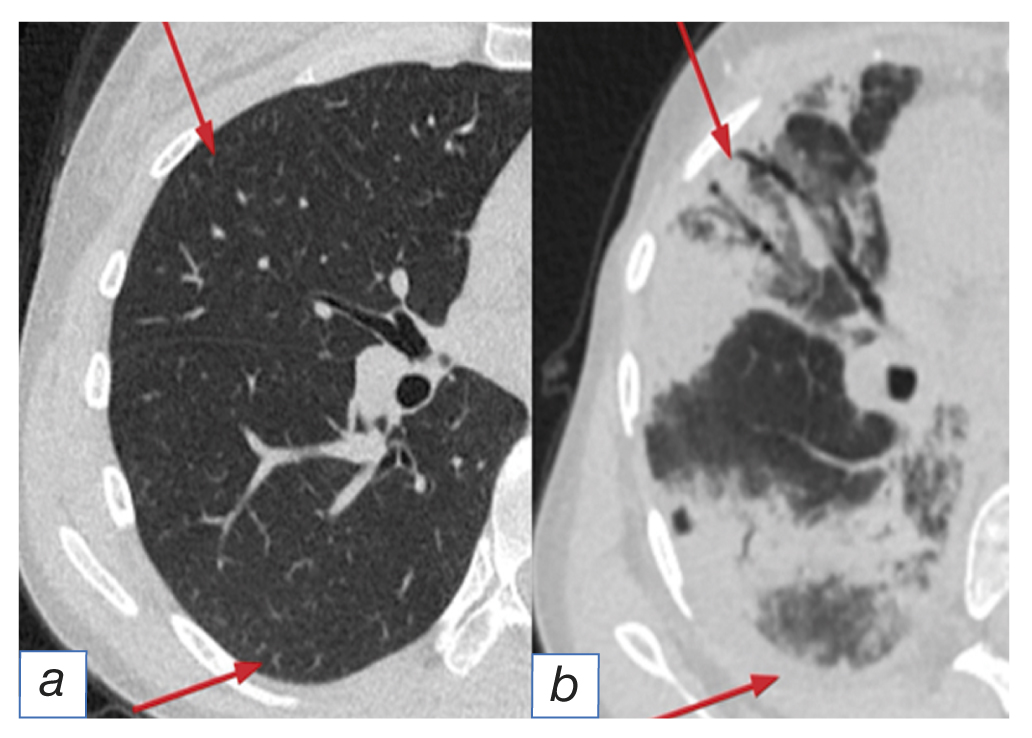

- the pattern of cryptogenic organizing pneumonia [3] visualized as focal consolidation with subpleural and/or peribronchial distribution and air bronchograms. The specific signs considered is the reverse halo (atoll sign) — foci of opacity (ground glass-type) at the center and consolidation along the periphery (Fig. 1);

Fig. 1. The pattern of cryptogenic organizing pneumonia: before (а) and after (b) immunotherapy (arrows).